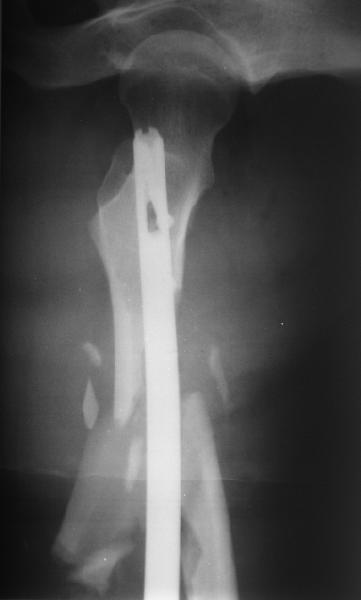

Уважаемые коллеги! От имени Алексея Смирнова всем спасибо за обсуждение. Больной прооперирован. Снимки в приложении.

Мы бы не стали открывать, такие переломы срастаются, хотя бы и с краевым дефектом. То есть если удалять стержень потом, то сильно попозже обычного. В приложении пример. Сразу после операции и через 11 мес. Понятное дело, пациент к тому времени давно и не хромал, и функция колена была полная.